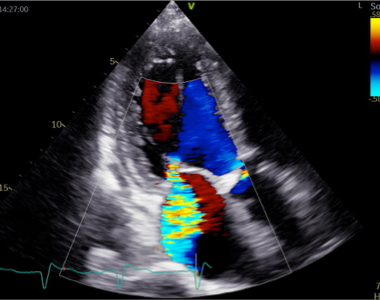

弁膜症の診断は、自覚症状が重要です。診察では、動悸・息切れ・疲れやすさなど、どの程度日常生活が制限されているかを問診します。さらに視診・触診を行って呼吸の状態や浮腫の有無を判断し、聴診により心雑音の有無と性状を確認します。弁膜症の検査は、胸部レントゲン写真・心電図・血液検査なども行いますが、なんといっても心エコー図検査は診断的価値が高いです。

心エコー図検査は体に害のない、痛みを伴わない検査です。どの弁が障害されているのかを特定し、その動きや狭窄・逆流の程度を診断します。同時に、心臓の部屋の大きさや機能を診断しますが、これらは治療方針に直結します。体に負担のない検査なので、治療後に繰り返し検査をして、どの程度改善しているかを評価することもできます。さらに、手術が必要な方には、心臓血管外科医が手術を行う際に必要となる様々な情報を提供します。

経食道心エコー図検査

経食道エコーでは、経胸壁からではわからないような細かい弁の異常や心内血栓を評価することができます。

近年、心臓外科手術の技術はますます向上しています。先進的な心臓外科手術に、経食道エコーは欠かすことのできない情報を提供するツールです。術前診断として弁の詳細な構造やその機能を評価し、手術デザインに役立てるとともに、手術中も経食道エコーを行って、外科治療の効果を迅速に診断します。